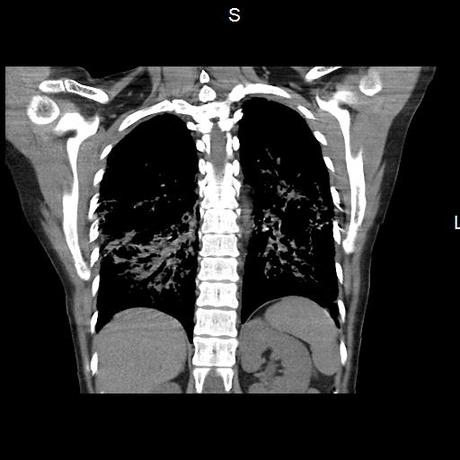

Se realiza volumen de tórax en fase simple, desde los opérculos torácicos hasta los hemidiafragmas, observándose:

El parénquima pulmonar con areas parcheadas difusas en vidrio despulido combinadas con otras areas hipodensas de baja atenuación debidas a atrapamiento aéreo y engrosamiento intersticial y zonas de fibrosis de predominio en lóbulos medios e inferiores de ambos pulmones.

- LOS HALLAZGOS PUEDEN ESTAR EN RELACIÓN A NEUMOPATIA INTERSTICIAL PROBABLE ETIOLOGIA HIPERSENSITIVA VS AUTOINMUNE/BACTERIANA/FUNGICA.